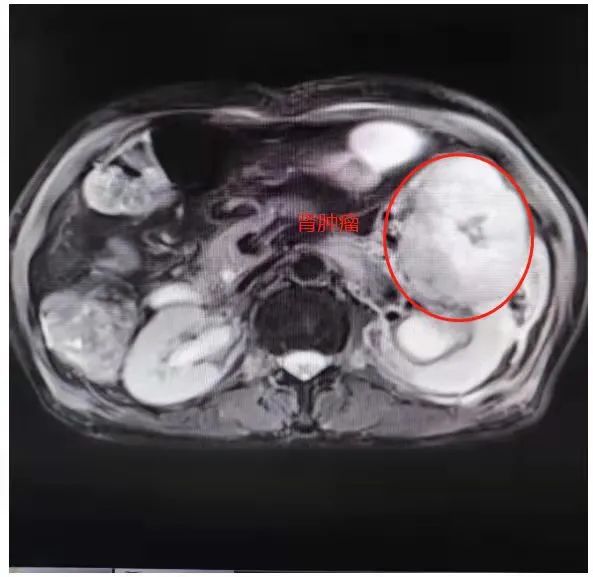

原来,在12月25日,86岁高龄的卿奶奶因突发血尿,到河池市人民医院泌尿外科就诊,经过一系列检查,确诊为:左肾透明细胞腺癌。根据卿奶奶的临床表现、体征及辅助检查,考虑恶性可能较大,保守治疗无效,需要进行手术治疗,因肿瘤较大,且卿奶奶合并有肾周感染、支气管炎、高血压、贫血、肠粘连等疾病,给手术增加了难度。

卿奶奶术前肾内肿瘤CT情况